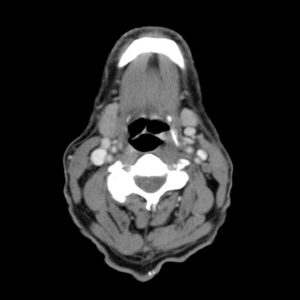

K hạ họng

Lượt xem: 241» 24-03-2019 -

K hạ họng

Lượt xem: 304» 24-03-2019 -

K hạ họng

Lượt xem: 198» 24-03-2019 -